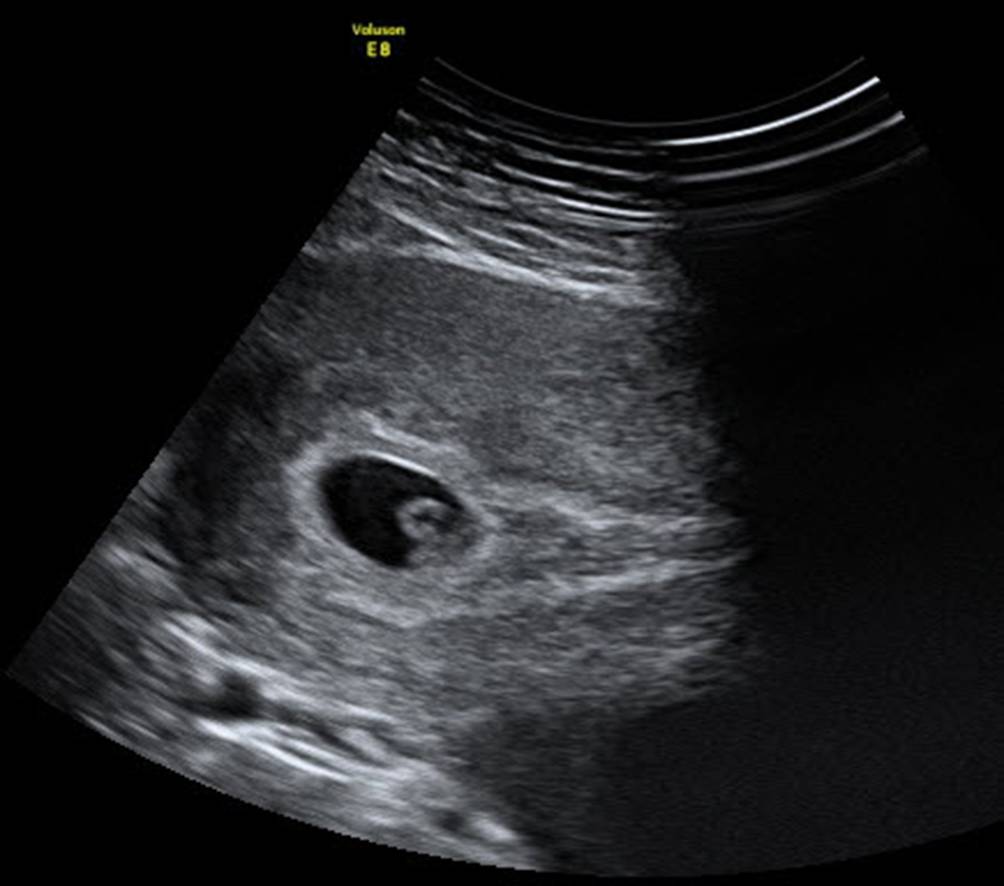

Abb. 5

Dermoidzyste im linken Adnexbereich von abdominal. Der echodense Streifen stellte sich dann als die für Dermoide typischen Haarbüschel heraus